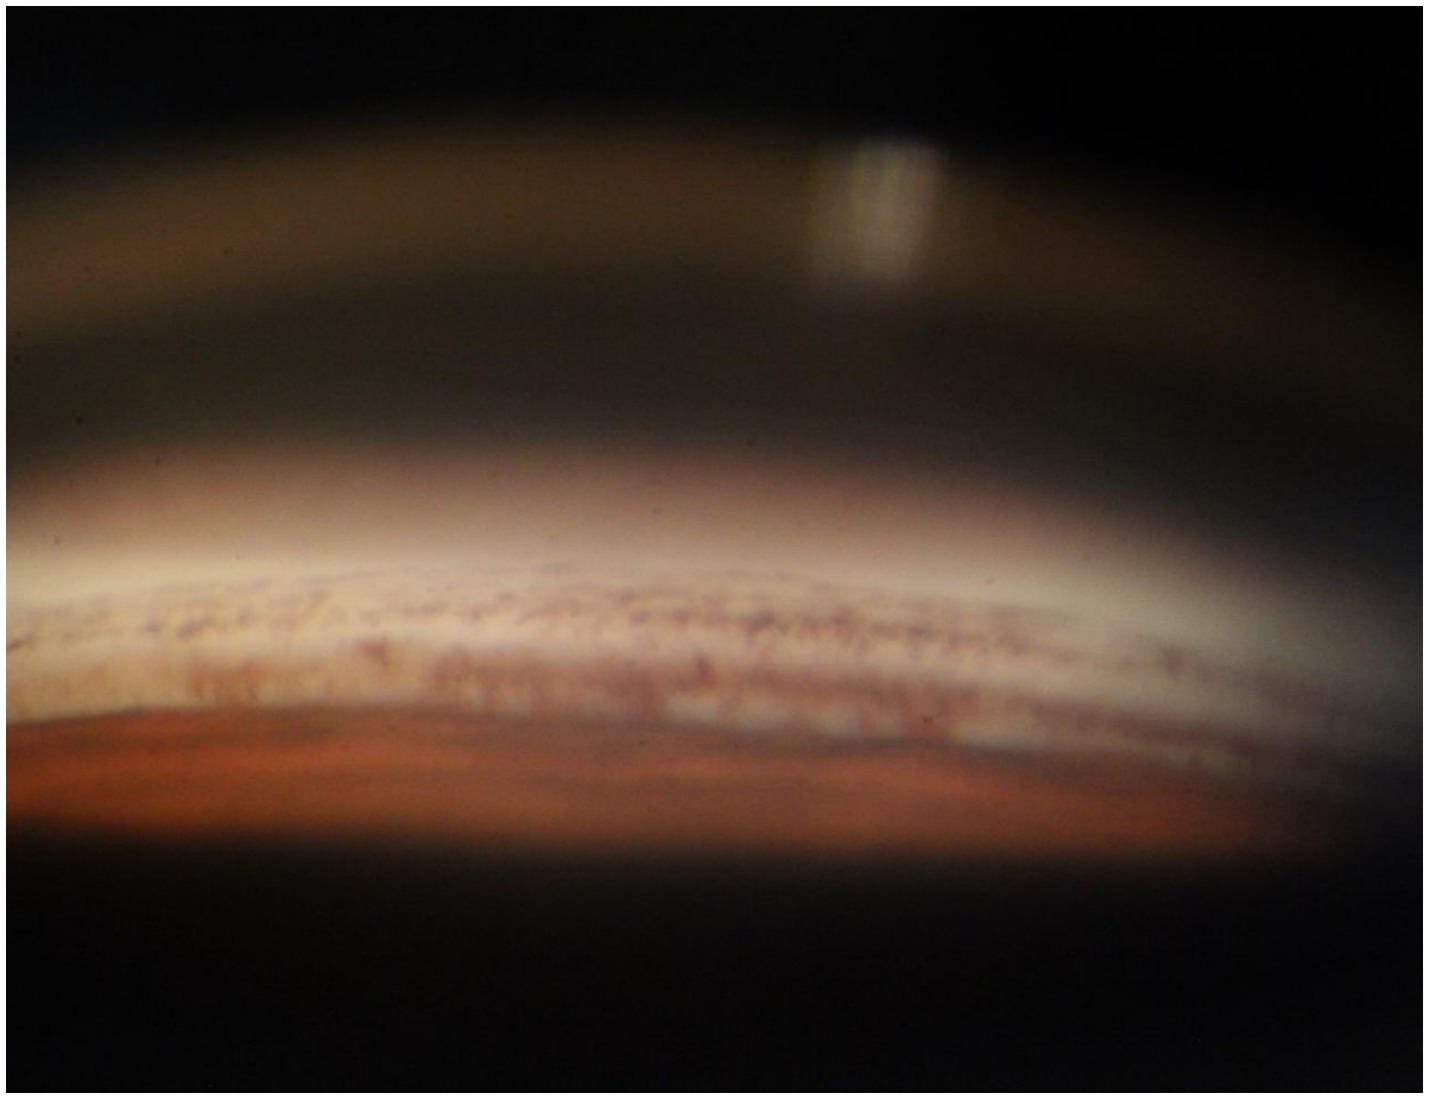

A 70-year-old Asian woman presented with left eye soreness and blurred vision for 1 month. When she first visited another hospital during this period, her visual acuity was 0.6 in the right eye and 0.1 in the left eye, with the intraocular pressure (IOP) being 15.2 mmHg in the right eye and 40.1 mmHg in the left eye, and she was diagnosed with left-eye glaucoma. Other ocular conditions at that time were unclear. She was treated with carteolol, brinzolamide, and pilocarpine eye drops for 1 month, but the therapeutic effect was unsatisfactory, so she visited our hospital. When the patient first presented to our hospital, the visual acuity of the right eye was 0.6, with an IOP of 17.1 mmHg, and that of the left eye was 0.6, with an IOP of 26.1 mmHg after using the aforementioned anti-glaucoma medications. The pupils of both eyes exhibited distinct miosis, likely caused by the medications. Considering that the patient was an elderly Asian female with an intumescent cataract, when we first saw her in the outpatient clinic, we initially thought the diagnosis was left-eye angle-closure glaucoma. However, we later discovered that the anterior chamber depths of both eyes were not shallow. It was not until we noticed unequal amounts of grayish-white debris on the pupillary margin of the left eye under the slit lamp (Figure 1). After careful consideration, we performed gonioscopy on the patient under topical anesthesia. We found that the angles of both eyes were open. Although this might have been due to the effect of pilocarpine, we also observed obvious pigment residues in the angles of the eyes (Figure 2). This alerted us to the possibility that the patient might have PEX. Ophthalmic evaluations were performed. Dynamic IOP monitoring revealed fluctuations of 17.1–20.1 mmHg in the right eye and 23.3–28.7 mmHg in the left eye despite treatment with two topical hypotensive agents. Fundus examination showed a red optic disc with a cup-to-disc (C/D) ratio of 0.4 in the right eye, whereas the left eye presented a pale-red optic disc with an increased C/D ratio of 0.7; both eyes had flat retinas with leopard-like fundus changes. Static perimetry (24–2 threshold test) demonstrated a visual field index (VFI) of 96% in the right eye (within normal range) and 66% in the left eye, with a superior arcuate scotoma in the left eye, classic for glaucomatous visual field loss. Optical coherence tomography (OCT) scans further confirmed: (1) in the right eye, no significant thinning of the macular neuroepithelial layer or ganglion cell layer (GCL), with only partial thinning of the retinal nerve fiber layer (RNFL); (2) in the left eye, partial thinning of the macular neuroepithelial layer, marked thinning of the GCL, and significant RNFL thinning—consistent with PEX-related glaucomatous optic neuropathy. Thus, based on the previous examinations, we dilated the pupils of both eyes. The dilation process was markedly difficult, which further strengthened our previous suspicion. Eventually, the anterior segment photographs after pupil dilation of both eyes are shown in Figure 3. We suspected that the development of the events was as follows: The grayish-white flakes on the periphery of the anterior lens capsule act like sandpaper on the iris, facilitating the release of a large amount of pigment from the iris. The released pigment will deposit and clog the trabecular meshwork (5). Upon detailed inquiry, the patient denied any relevant family history.

Figure 2. Anterior chamber angle of the patient’s left eye. A large amount of pigment is densely distributed around the trabecular meshwork tissue. These pigments will impair the external filtration function of the trabecular meshwork.